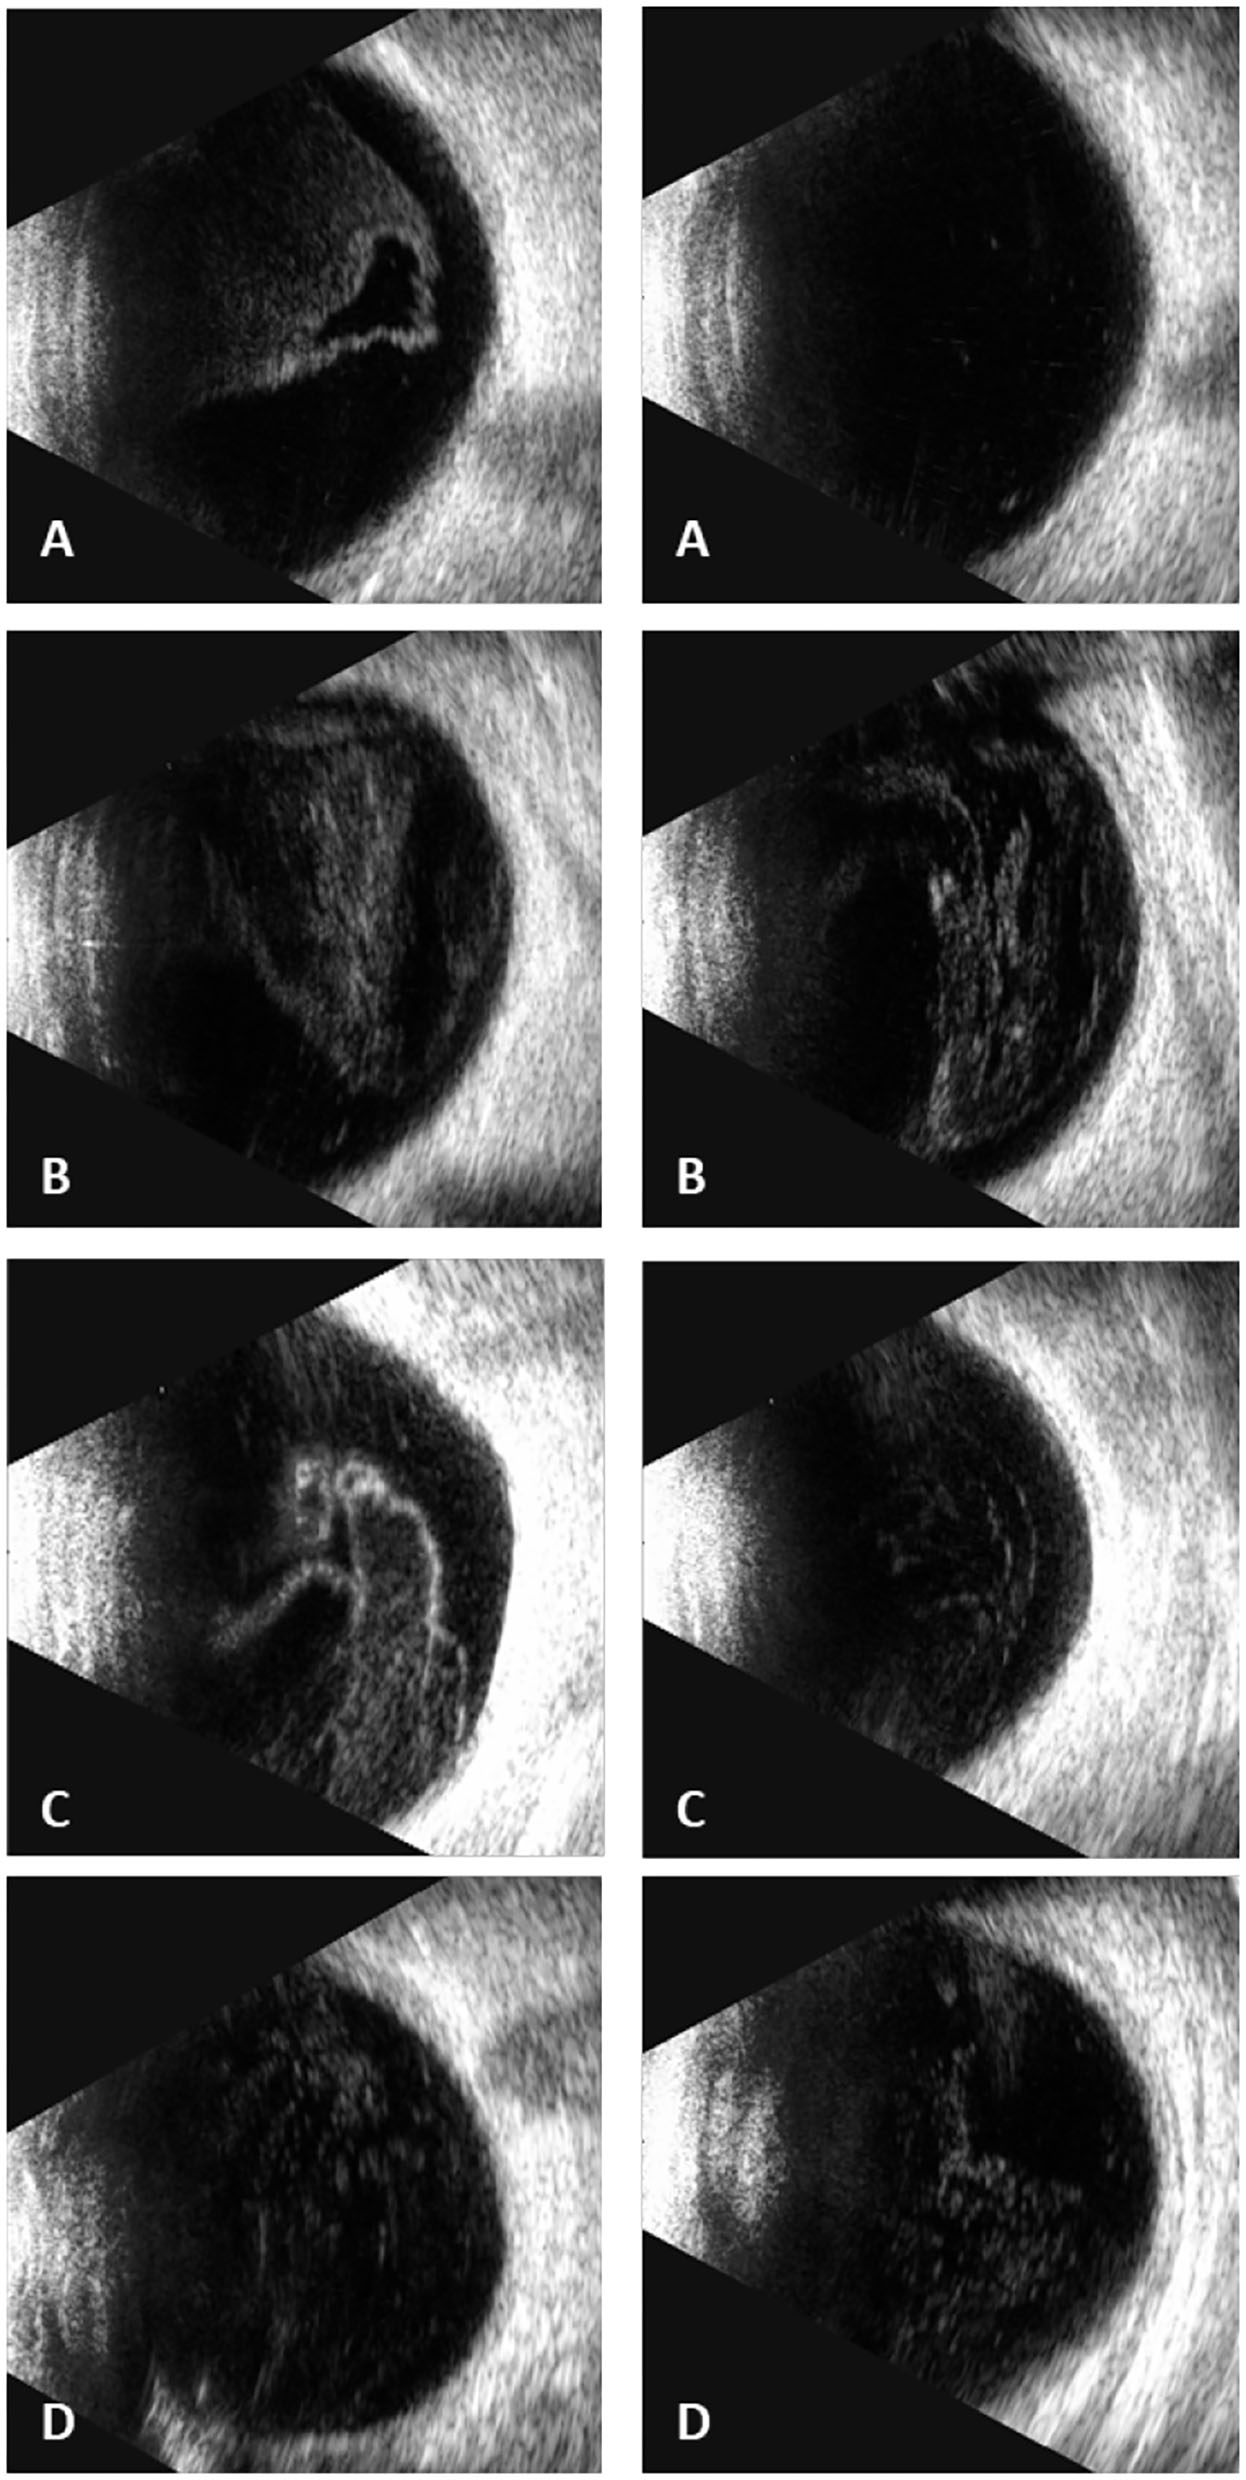

Figure 3

Ultrasound B scans demonstrated severe vitritis in all four patients [(A) patient one, (B) patient two, (C) patient three, (D) patient four] (Left: the right eye; right: the left eye) [(D) shows only the left eye for the atrophy of the right eye].

In our study, all four patients were progressed with active CMVR lesions with immune recovery within 8 weeks of HAART initiation. Characteristics of the four CMV-IRR patients with HIV positive are summarized in Table 1. Among the four patients, the mean CD4 T cells were 14.5/μl at the HIV diagnosis and 183.25/μl at the CMV-IRR diagnosis. All four patients had an obvious increase of CD4 T cells over 100/μl from a very low baseline (<40/μl). They came to our ophthalmology department and presented with progressed blurred vision without any ophthalmological examination or treatment. The slit lamp showed vitritis and retinitis without anterior segment abnormalities. The vitreous activity was evaluated according to the grading system (1+ to 4+) proposed by Nussenblatt et al. (7). Fundus examination including mydriasis fundus examinations, ultrasound B scans, and OCT scans was performed in the four patients. The fundus showed typical necrotizing retinitis, intraretinal hemorrhages, and vasculitis (Figure 1, patient four). Three patients had retina lesions in zones 2 and 3, while the other patient had retina involvement in zones 1–3. OCT showed normal in one patient and a slight epiretinal membrane in macular in two patients. The other patient had a minor retinal neurosensory layer detachment in the macular (Figures 2A–D). Ultrasound B scans demonstrated obvious vitritis in all four patients (Figures 3A–D). PPV was done and vitreous samples were aspirated for next-generation sequencing. The results demonstrated a high copy of the CMV sequence ranging from 60,527 to 445,532.